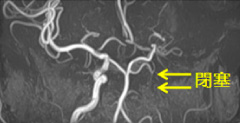

頭部MRA

頭部MRA

手術前

手術前 手術後